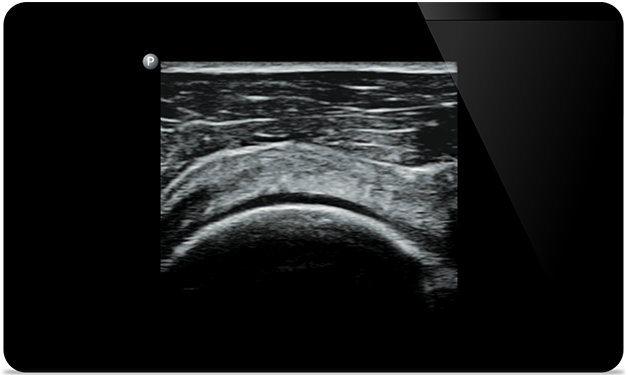

Lumify helps you see the fine details in muscles, joints, ligaments, tendons and cartilage to make a more accurate diagnosis of injuries.

Lumify can help you assess patients from head to toe, whether it’s plantar fasciitis, tendonitis or bursitis in the patellar tendon, or even shoulder instability in the rotator cuff.

Ultrasound-guided

knee arthrocentesis

Ultrasound-guided hip arthrocentesis